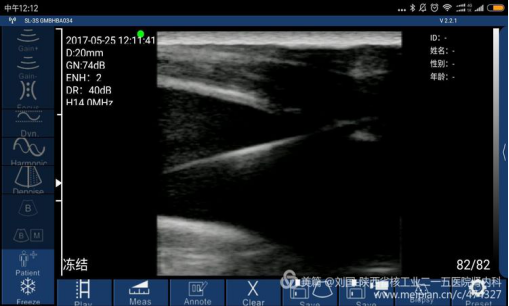

case 3:索诺星无线超声经WiFi连接小米max,同步引导带cuff的颈内静脉留置导管的置入